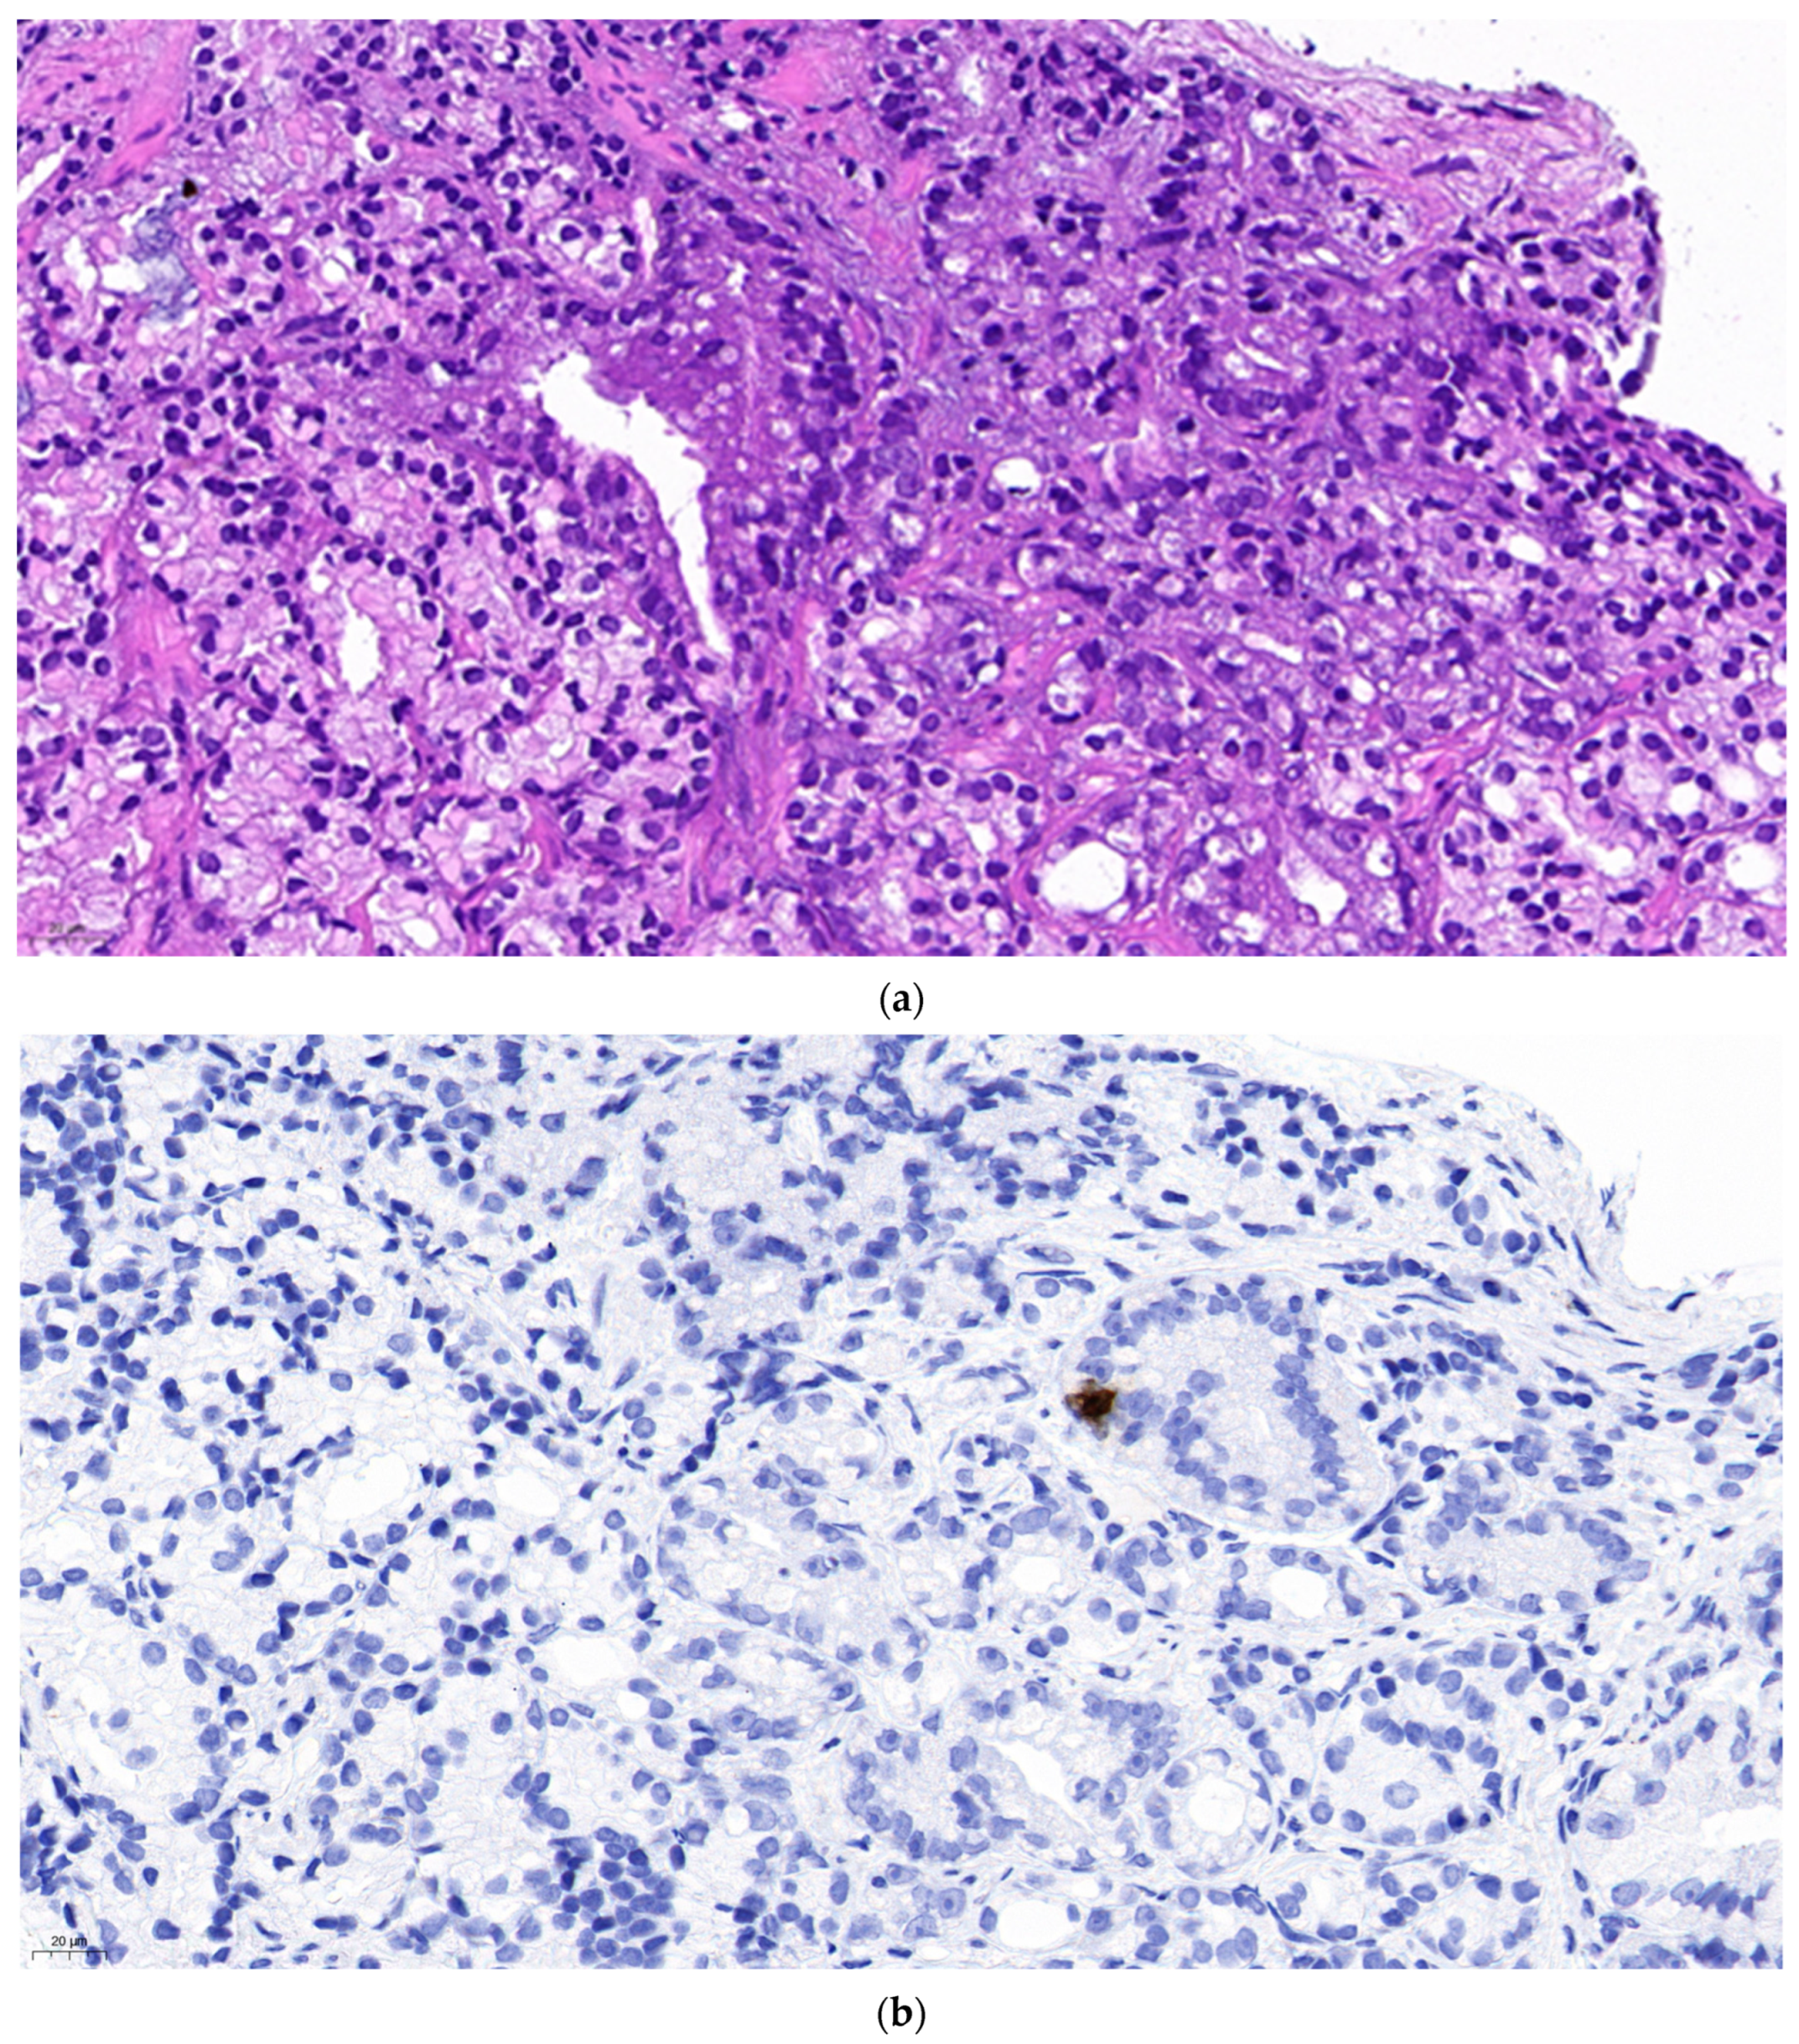

Figure 2a represents a primary prostate cancer (Gleason grade group 5). Figure 2b shows positivity of chromogranine A IHC staining. Figure 2c is the superposition of the two above figures showing clearly that only a part of the malignant cells are stained and thus have neuroendocrine feature. The remaining part is common adenocarcinoma. This figure demonstrates a primary mosaic prostate cancer. The patient was prostatectomised after receiving 3 cycles of primary cisplatin-etoposide treatment. The prostate did not show any positivity at neuroendocrine IHC, meaning that the neuroendocrine component was in complete pathological regression after chemotherapy. Currently we observe a slight increase of NSE while the PSA remains suppressed and staging examinations are negative.

Figure 2. Biopsy specimen of a prostatic mosaic neuroendocrine-/adenocarcinoma. (a). Haematoxylin-eosin staining. (b). Chromogranine A immunohistochemistry showing numerous positive cells in the malignant zone. (c). Superposition of Figure 2a,b. Δ showing adenocarcinoma cells, ▲ showing malignant neuroendocrine cells, the yellow circle showing a normal glandular zone.

The presented superposed images were realised with the Inkscape vektographic drawing software. The lower layer was the hematoxylin-eosin stained (Merck reagent) in normal mode, the upper layer was the chromogranine A stained (Cell Marque reagent, Dako autostainer) in darken mode.